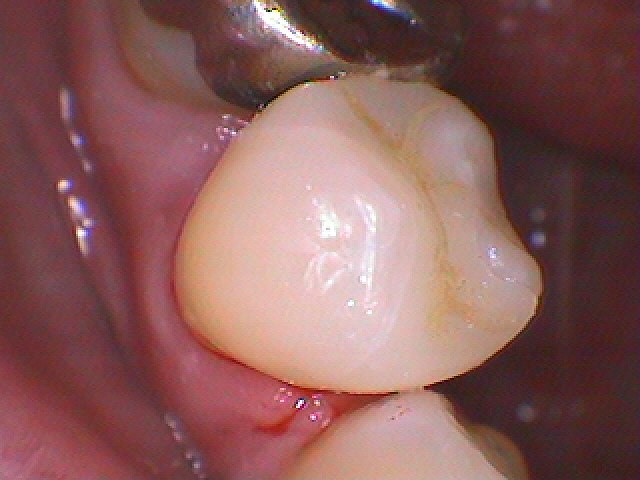

銀歯を外していきました

悪いところを除去していきました